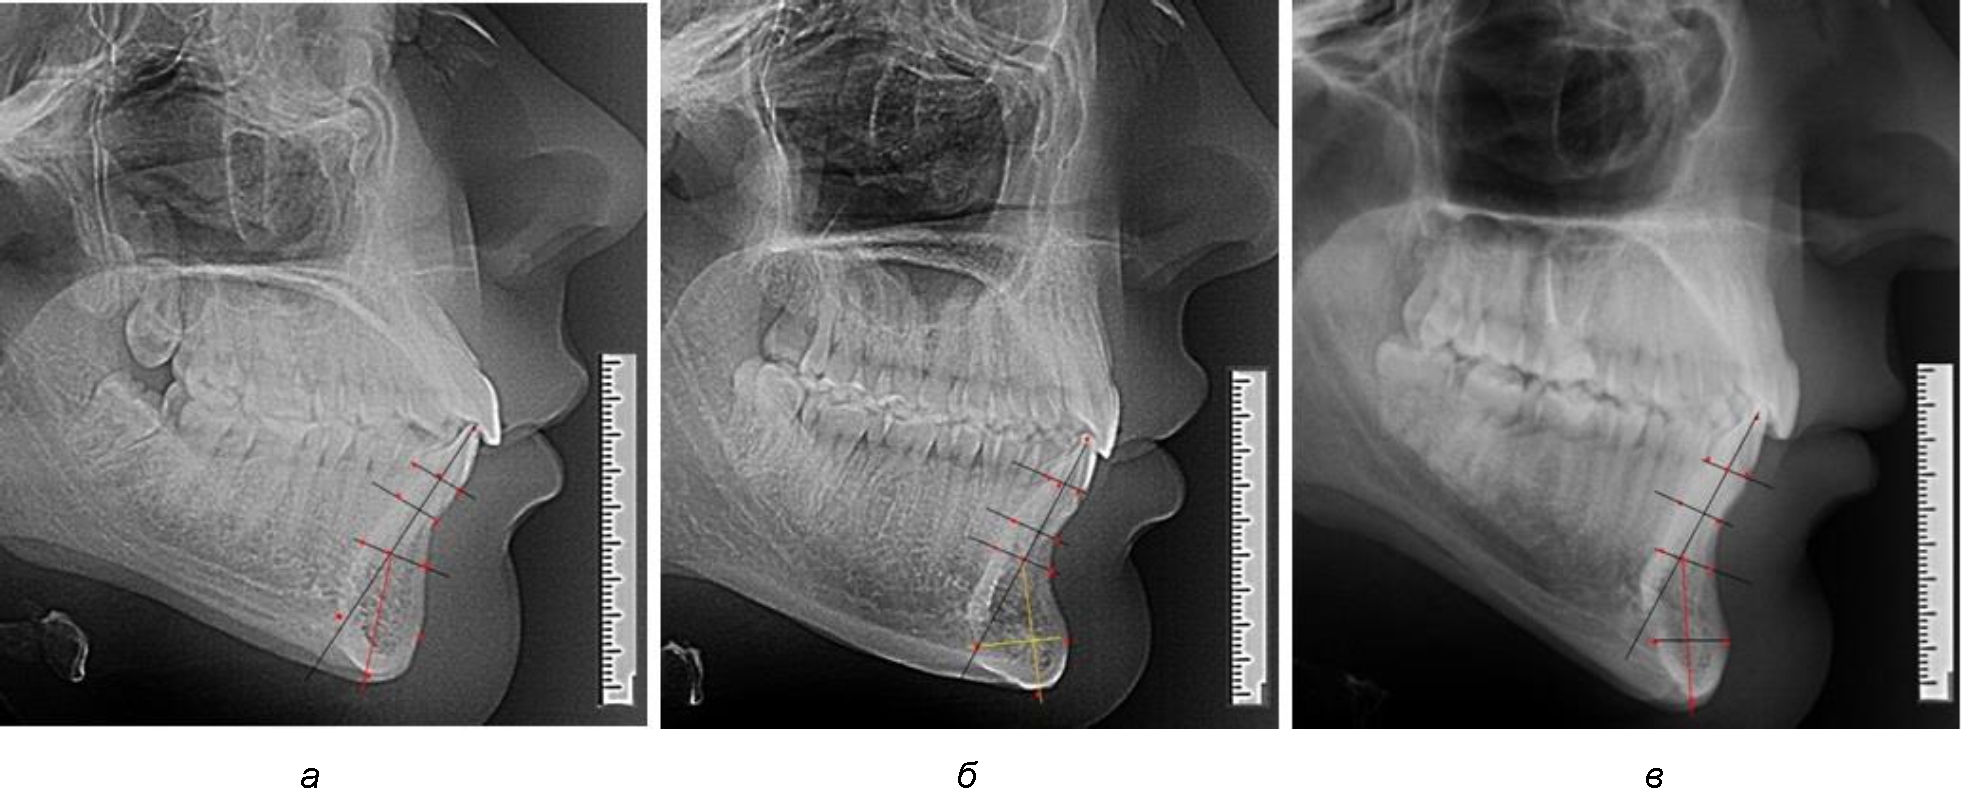

На нижнем контуре подбородочного выступа определяли положение ментальной точки Me. Линия, соединяющая апикальную точку с ментальной, определяла высоту подбородочного выступа тела нижней челюсти. Высота зубочелюстного сегмента IsL–Ме измерялась от резцовой до подбородочной точки. Вертикальная линия Ap–Me делила подбородочный выступ на две части: переднюю и заднюю (рис. 1).

Рис. 1. Ориентиры для исследования нативных препаратов (а) и рентгенограмм (б) резцового нижнечелюстного сегмента

Сагиттальные размеры зубоальвеолярной части сегмента определялись между точками Bsm и Bsm', в апикальной части сегмента – B и B'. В подбородочной части сегмента из передней выступающей точки подбородка Pog проводили линию перпендикулярно к линии Ар–Ме с определением точки Pog'. Расстояние Pog–Pog' определяло ширину подбородочного выступа.

При анализе боковых телерентгенограмм использовали фрагменты гнатической части, на которых оценивали вертикальные и сагиттальные параметры резцового нижнечелюстного сегмента, на который наносили те же ориентиры, что и при анализе нативных препаратов и их рентгенограмм.

При необходимости и/или возможности проведения КЛКТ-исследования проводили анализ с сопоставлением фрагмента, что повышало точность диагностических мероприятий (рис. 2).